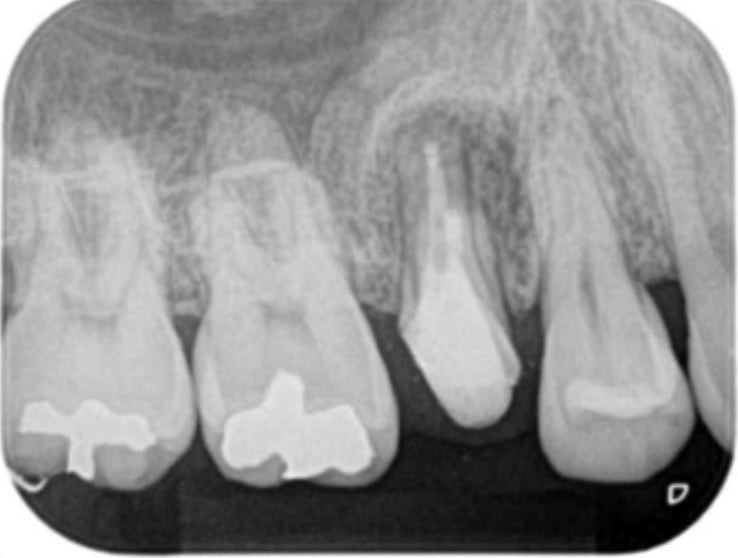

A comparison of survival of teeth following endodontic treatment performed by general dentists or by specialists

Bradley S Alley, DMD, G Gray Kitchens, DMD, Larry W Alley, DMD, Paul D Eleazer, DDS, MS

Oral Surgery,Oral Medicine,Oral Pathology,Oral Radiology,and Endodontology Volume 98, Issue 1, July 2004, Pages 115-118